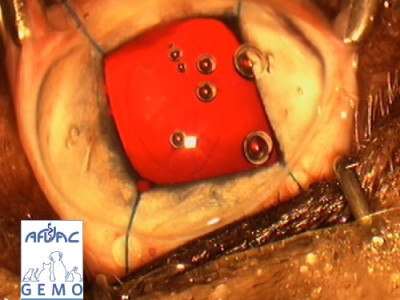

Une belle journée de chirurgie oculaire en perspective!

Si vous vous intéressez à la chirurgie oculaire, cette journée est pour vous !!